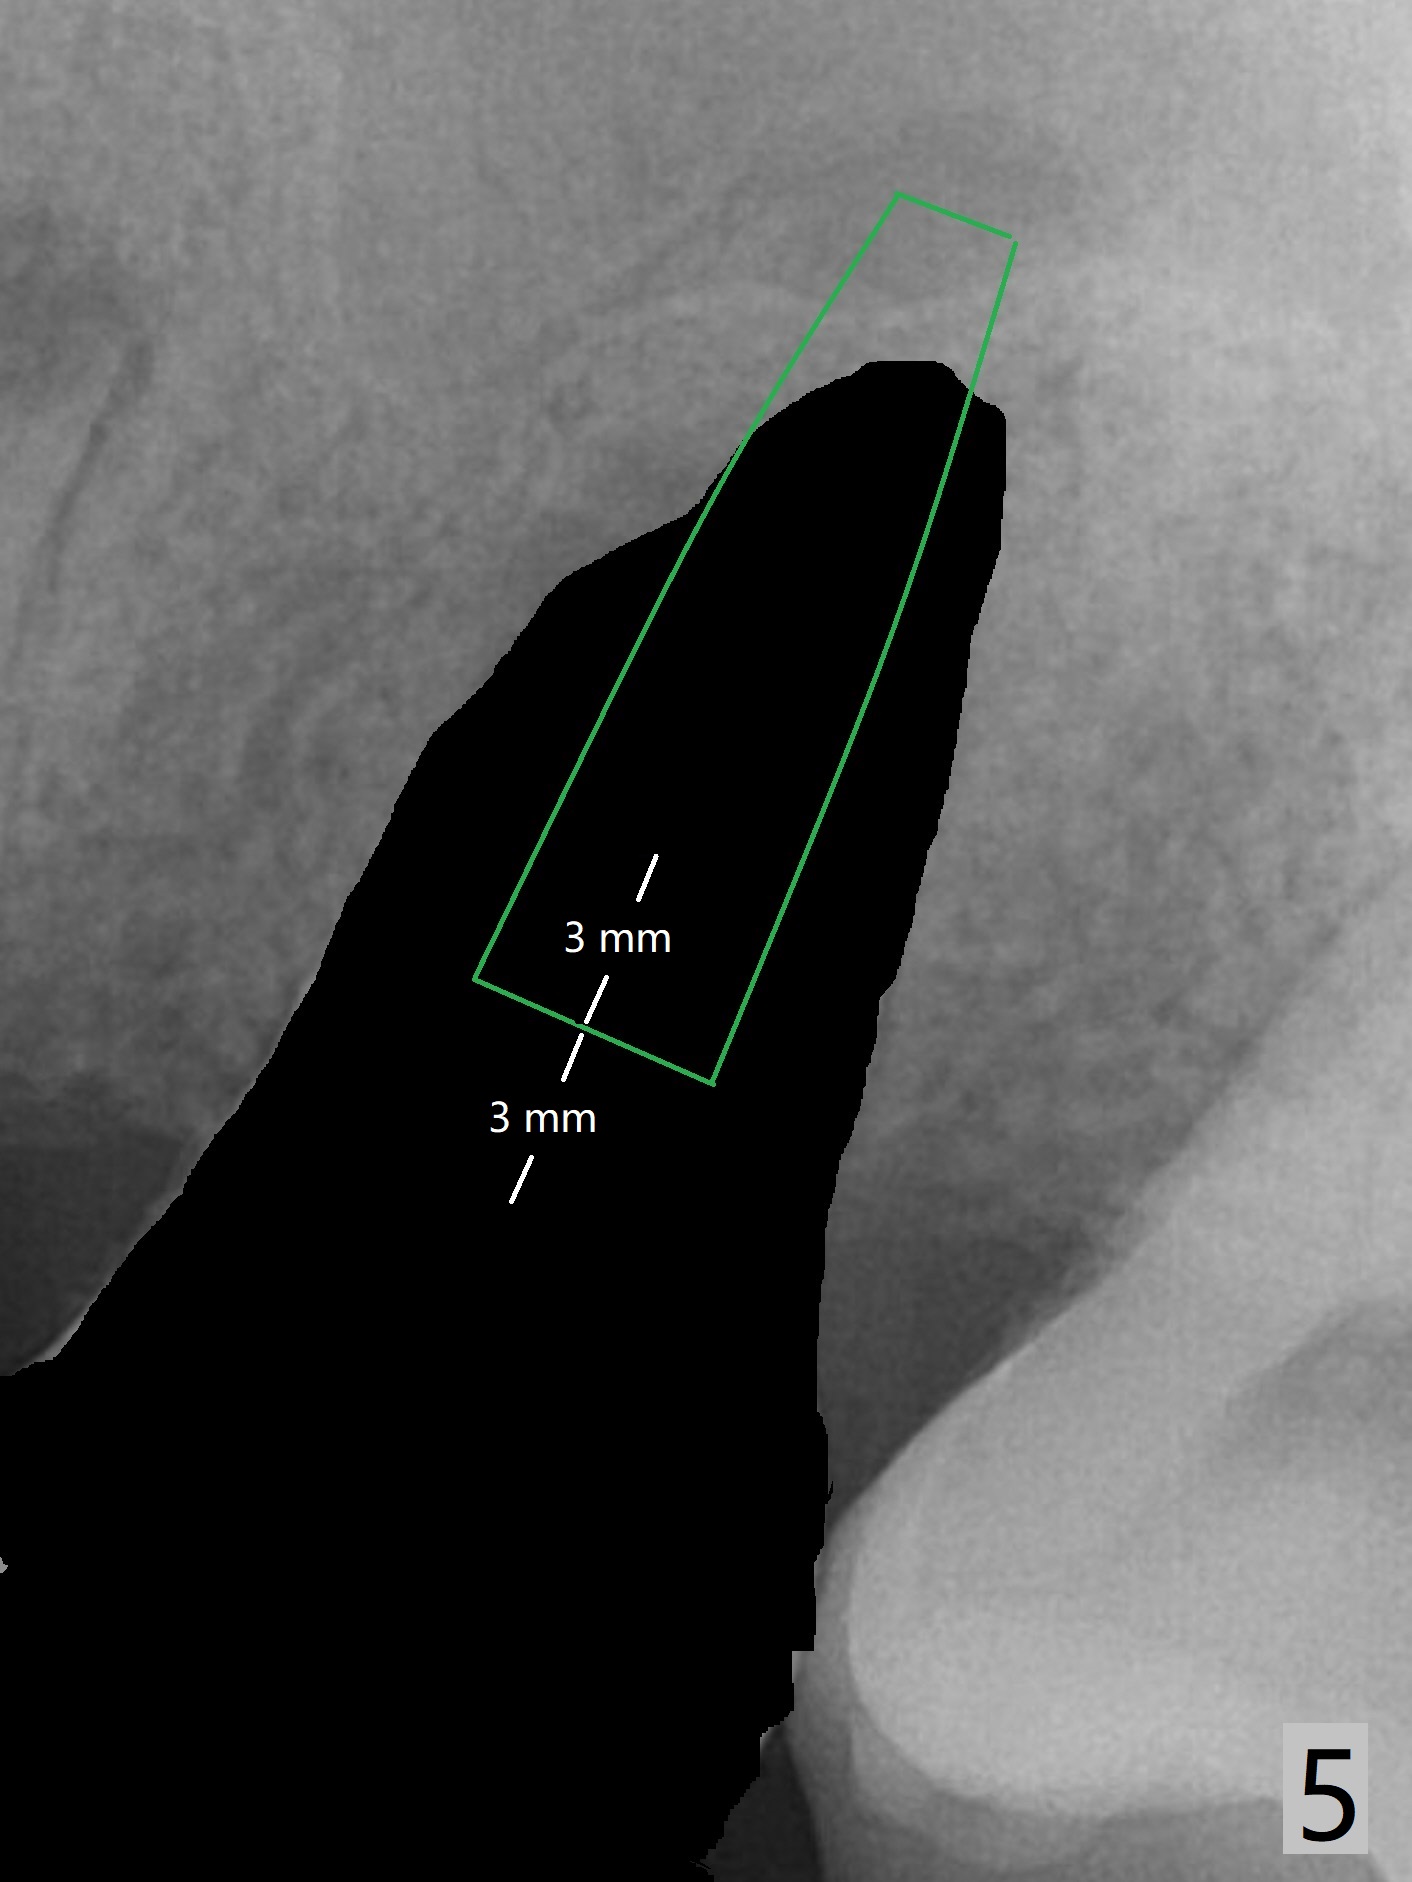

A 45-year-old man has chronic generalized moderate localized severe periodontitis; gingival recession is severe lingual of the tooth #14 with mobility II (Fig.1). The low bone density outline (Fig.1 white dashed line) is larger than the roots, suggesting lingual bone loss/low lingual crest. Although the bone height seems to be 11 mm (Fig.2), the bone responsible for primary stability of an implant will be apical (Fig.3 *,4). The implant platform will be ~3 mm subcrestal buccal, while ~3 mm supragingival lingual (Fig.5). The diameter of the implant will not be too large, 4.5 mm (dummy). There will be not biologic width issue. The large perimplant gap will be closed with sticky bone. Severe palatal gingival recession is shown pre- (Fig.6) and post- (Fig.7) SRP. #30 Gutta Percha inserted palatal reaches the highest point of the low bone density lesion (Fig.8). Pulpal test and CT will determine that endodontic treatment can regrow bone or that socket preservation is needed with Cytoplast.